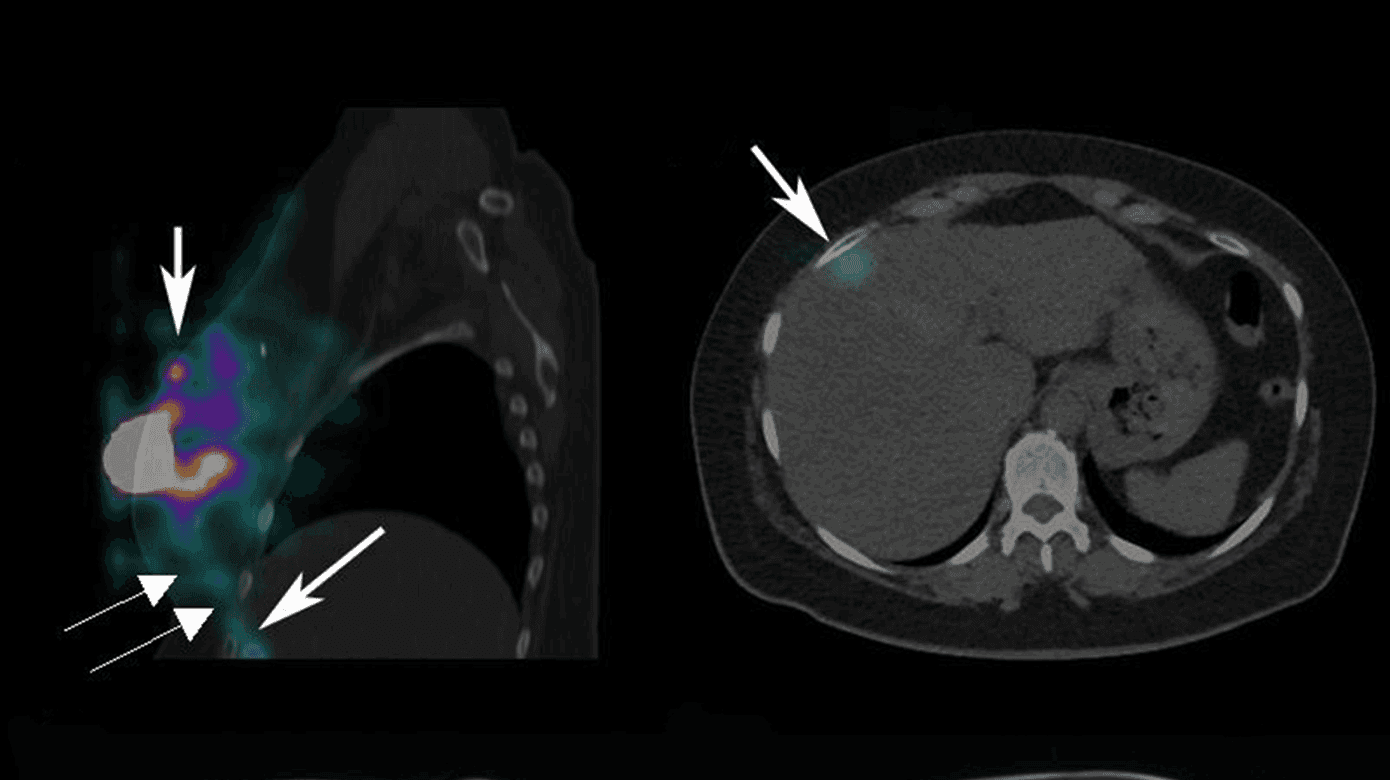

Præoperativ SN-LS med SPECT/dæmpningskorrigerende CT visualiserede ingen SN i aksillerne, mammariagebetet, subpektoralt eller periklavikulært, men aktivitet i en bane lateralt for og parallelt med m. rectus abdominis dxt. strækkende sig fra brystet til et fokus på 3 mm i leverens segment VIII/IVa (Figur 1). Den abnorme drænage rejste mistanke om leverinvolvering. Den efterfølgende MR-skanning viste tre metastasesuspekte foci i henholdsvis leverens segment VIII/IVa, VI og II/III, hvilket blev bekræftet ved UL-vejledt biopsi, som viste IDC med samme receptorprofil som primærtumoren og recidivet.